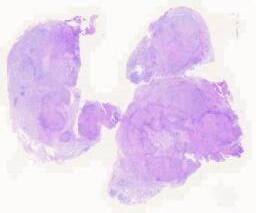

大体所见: 灰黄灰白碎组织一堆,大小3.2 cm×2.5cm×1.5cm,切面灰黄质中,局部见囊壁样物。